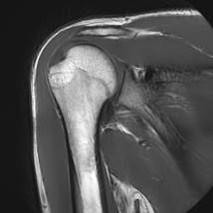

MRI(Magnetic Resonance Imaging/磁気共鳴画像)は、強力な磁石と電波を用いて体の内部を詳しく撮影する検査です。

放射線被ばくがなく痛みもない安全な検査です。通常20~40分程度で終わります。

脳だけでなく、全身のさまざまな部位の検査が可能です。

脳・脊椎・関節・四肢・腹部・骨盤・乳腺など幅広い部位に対応しています。

当院では最新の3テスラMRI装置を導入しており、従来の1.5テスラ装置とあわせて検査内容に応じた撮影を行っています。

3T MRIでは、高精細でより詳細な画像診断が可能です。